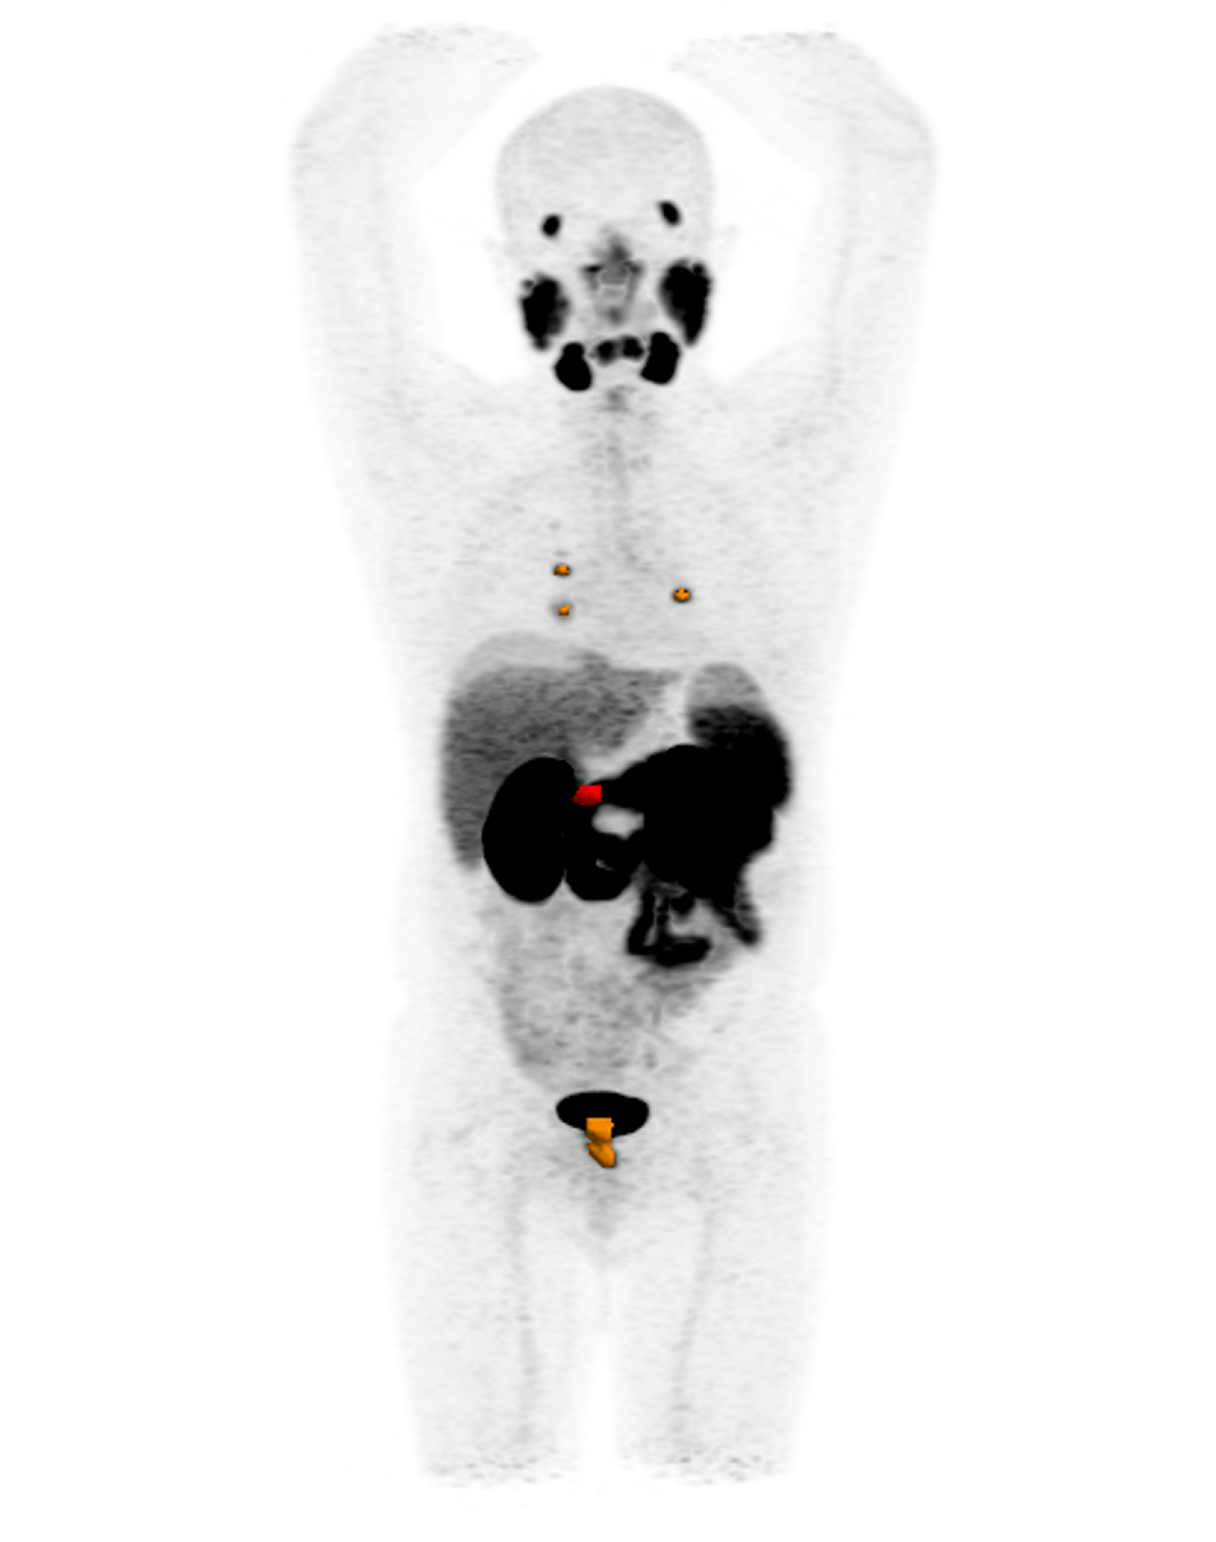

La velocità di progressione della fibrosi cardiaca: un nuovo orizzonte

La velocità di progressione della fibrosi cardiaca emerge come un nuovo e cruciale indicatore prognostico nella cardiomiopatia ipertrofica. Un recente studio evidenzia come l’LGE rate sia più predittivo degli eventi avversi rispetto alla semplice estensione della fibrosi, aprendo nuove prospettive per il monitoraggio e la gestione terapeutica dei pazienti.